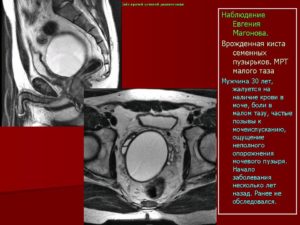

Для диагностики чаще применяют ТРУЗИ (трансректальное ультразвуковое исследование). Если есть подозрение на злокачественный процесс, выполняют магнитно-резонансную томографию, позволяющую дать оценку отношению кисты (опухоли) к близлежащим тканям.

МРТ — более информативный метод, но учитывая его высокую стоимость, к магнитно-резонансной томографии прибегают только при подозрении на рак простаты.